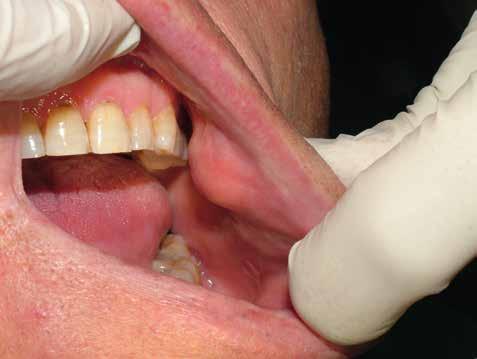

Deve prevedere sia l’osservazione sia la palpazione di tutte le mucose orali, partendo da labbra, lingua, guance, per arrivare alla valutazione del tessuto gengivale dei fornici, del palato e la gengiva aderente. Se ne devono valutare colore (fig. 11 ittero mucoso), fragilità, consistenza e presenza di ulcere o tumefazioni.

L’esame clinico rappresenta sicuramente la fase di analisi più complessa in quanto i parametri da valutare sono molti e possono interessare tutte le specialità odontoiatriche. Sono da valutare lo stato di salute della dentatura residua, la presenza o meno di manufatti protesici, il rapporto intermascellare,

lo stato di igiene orale, la condizione dei tessuti parodontali, le abrasioni dello smalto che ci indirizzino verso la diagnosi di parafunzioni come il bruxismo, la limitazione nell’apertura della bocca o la presenza di deviazioni per disordini temporo-mandibolari. (Figg. 16-21)

FIG. 17 FIG. 16 FIG. 19 FIG. 18 FIGG. 16-21: Valutazione FIG. 21 FIG. 20